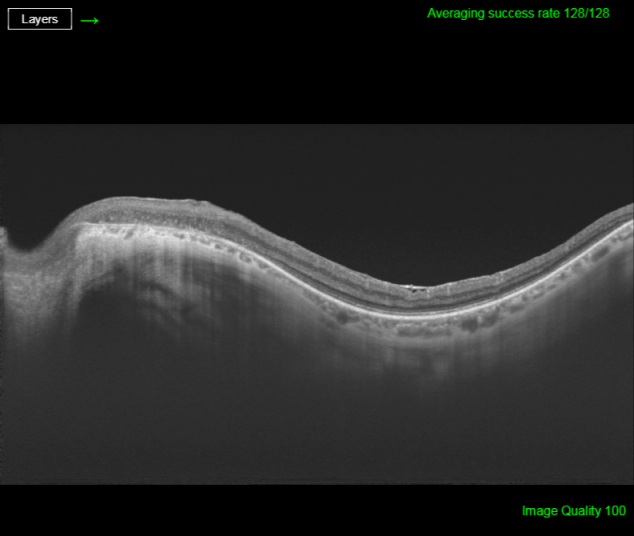

His best corrected visual acuity (BCVA) was 20/32 (Snellen chart) in his right eye (OD) and 20/63 in his left one (OS). Anterior segment was unremarkable for both eyes (OU). Fundus evaluation showed pigment clumps along the retinal veins with variable chorioretinal atrophy extending from the disc up to the equator in both eyes (clinically more evident in OS). Fundus autofluorescence (FAF) imaging revealed hypo-autofluorescent areas corresponding to the atrophic patches over the posterior pole (Figure 1 [Fig. 1] and Figure 2 [Fig. 2]). SS-OCT showed a preserved foveal profile and great macular atrophy in OU, but serious involvement of the retinal outer layers in the left eye (Figure 3 [Fig. 3] and Figure 4 [Fig. 4]). In Angio-OCT, severe involvement of the ellipsoid, choriocapillar, and avascular layers could be appreciated in OS.

Figure 3: SS-OCT image of the right eye reveals external retina altered with an increase of choroidal signal due to retinal pigment epithelium atrophy.

Figure 4: SS-OCT age of the left eye exhibits external retina damage with an increase in choroidal signal due to retinal pigment epithelium atrophy

SS-OCT scans normally reveal thinning of retinal layers with increased backscattering and disorganization of the RPE choriocapillaris complex. In many occasions, as we can see in our case, retinal and choroid slimming is such severe that scleral looks like very thick. Hyperreflective plaques with underlying shadowing corresponded to the pigment clumps observed clinically [10]. OCT-A study is not correctly defined yet and we do not find explanatory signs in our patient.